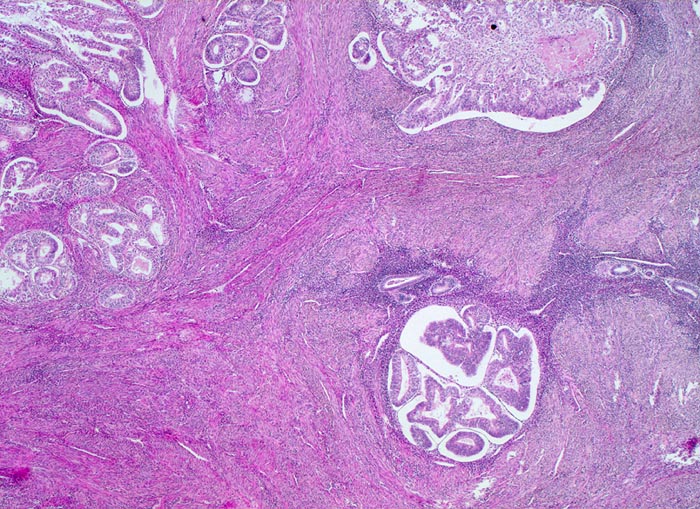

endometrioides Adenokarzinom mit Ausbreitung in Adenomyoseherden

Oben links im Bild das muskelinvasive hoch differenzierte endometrioide Karzinom. Rechts im Bild Adenomyoseherde mit Karzinomdrüsen. Die malignen Drüsen sind von endometranem Stroma umgeben, also nicht invasiv und verschlechtern somit die Prognose nicht.